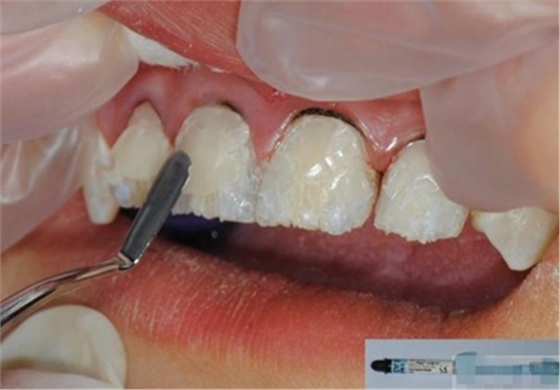

【酸蝕粘結(jié)】

使用磷酸酸蝕可用完全去除玷污層,粘結(jié)劑可用充分滲透到牙本質(zhì)小管中。用自酸蝕系統(tǒng)則達(dá)不到這一點(diǎn),由于其不能充分去除玷污層,粘結(jié)劑向牙本質(zhì)小管內(nèi)的滲透率低。所有的研究均顯示,使用全酸蝕系統(tǒng)所形成的粘結(jié)混合層要比使用自酸蝕系統(tǒng)厚。

酸蝕處理的時(shí)間

a,活髓牙本質(zhì)酸蝕30秒;

b,硬化牙本質(zhì)酸蝕60秒;

c,根管內(nèi)如果需粘結(jié)根冠樁,需酸蝕2分鐘。